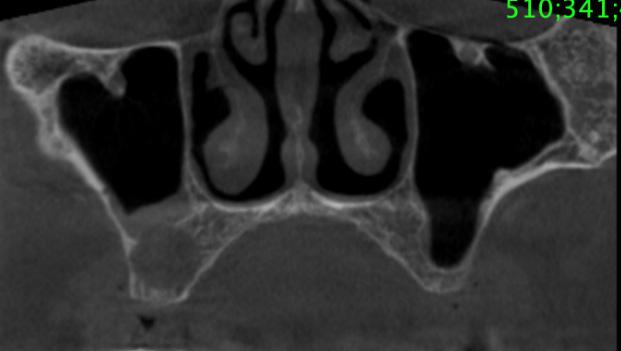

Durante el estudio, la cabeza de cada estudiante fue posicionada en relación al plano de Frankfurt (paralelo al piso), mismo que se logró con una regla nivel de 30 cm; dicho plano anatómico se extiende desde el agujero infraorbitario a la parte media del borde superior del conducto auditivo externo (12), estos reparos anatómicos se identificaron en el estudiante mediante la palpación digital del borde inferior de la órbita y a simple vista del trago del pabellón auricular (figura 1).

Quelca-Portugal-Yujra-Chuquimia

Seguidamente y mediante palpación se localizó de forma bilateral el ángulo mandibular, el reborde orbitario lateral y la arteria facial de cada estudiante, ésta última estructura se identificó a nivel del borde inferior del maxilar inferior, percibiendo sus pulsaciones con facilidad. Con un lápiz dermográfico se marcó un punto en la piel donde se localizó a estas tres estructuras. Desde el punto marcado que representaba a la arteria facial, se trazó una línea vertical y ascendente hasta la referencia anatómica más relevante, identificable y no modificable por procesos infecciosos submandibulares (arco cigomático). Finalmente se determinó la distancia entre el borde lateral de la órbita y la proyección vertical ascendente de la arteria facial sobre el arco cigomático (figura 1).

Fuente: Elaboración propia, julio 2019

Figura 1. Puntos y líneas utilizadas para la localización de referencia anatómica no modificable sobre la base de la arteria facial. Localización de referencia anatómica inmodificable sobre la base de la arteria facial en infecciones submandibulares odontogénicas